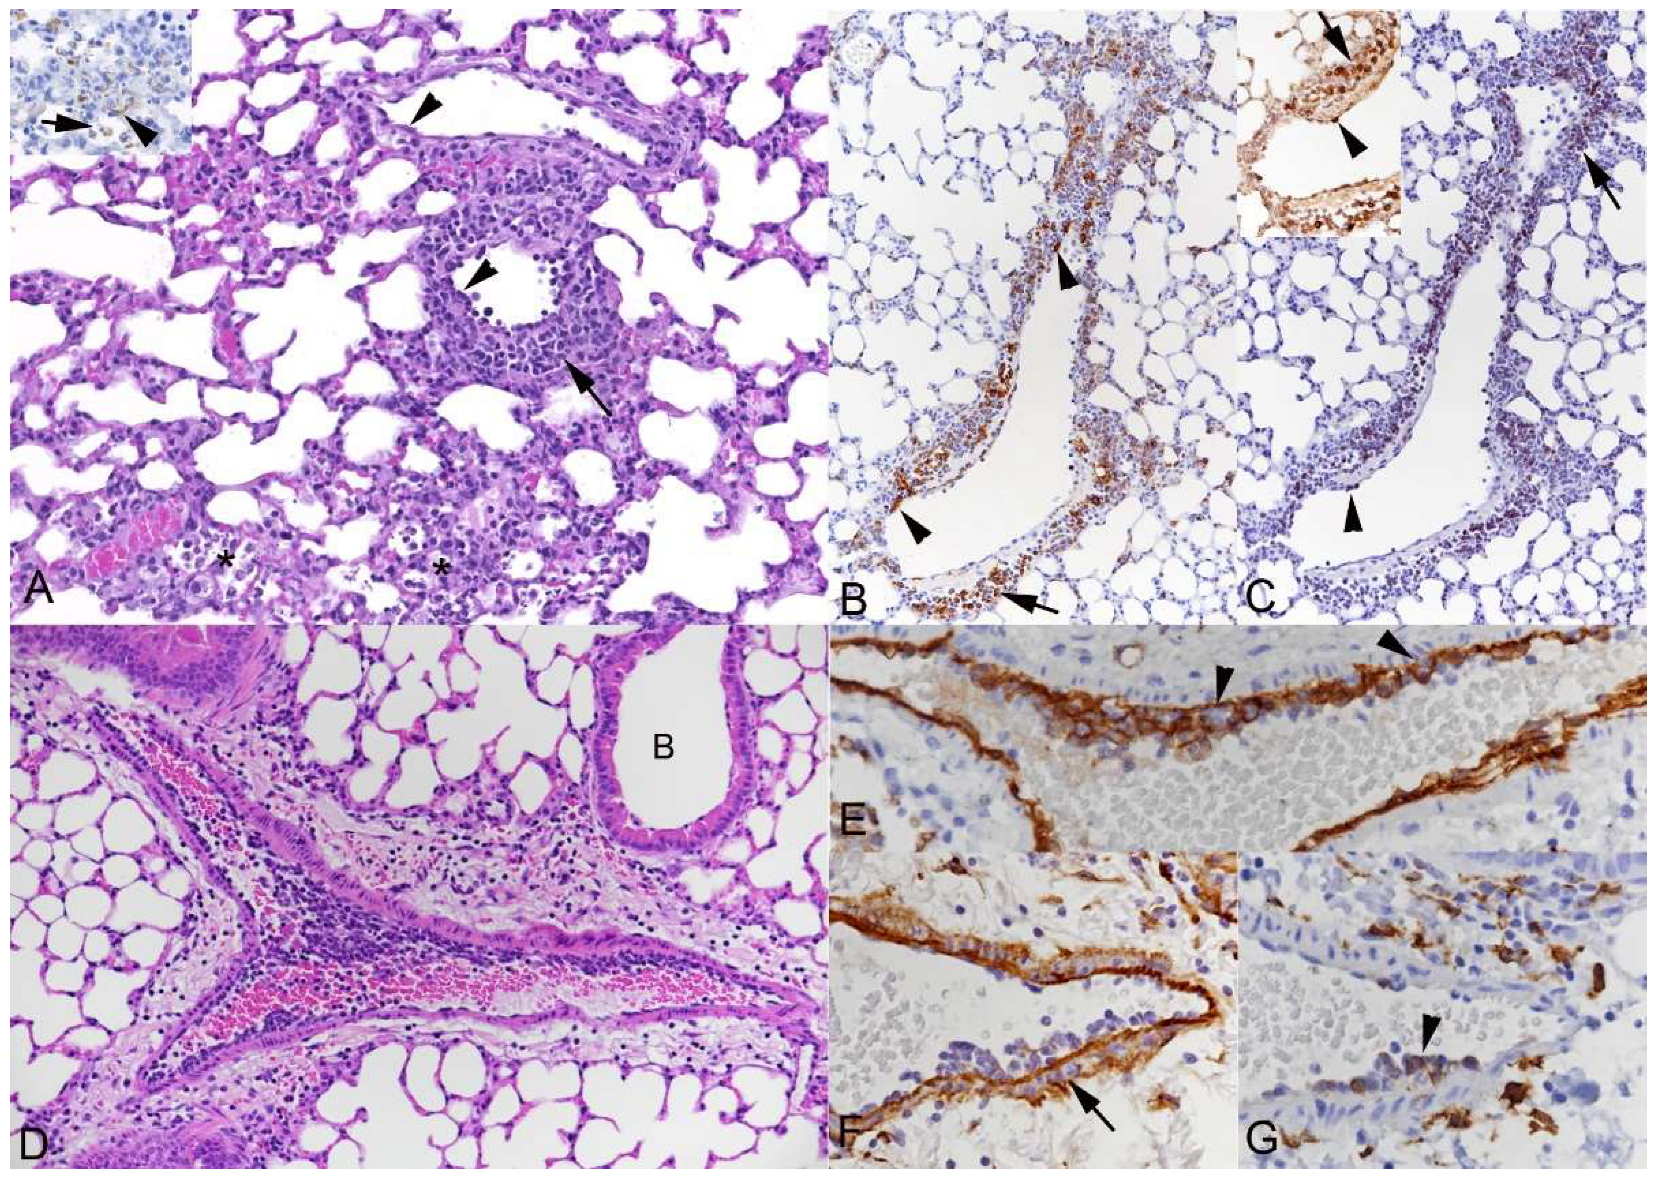

3.1. Pulmonary Vasculitis Is a Consistent Feature of SARS-CoV-2 Infection in Mouse Models

3.2. Respiratory Virus Infections, with Variable Degree of Alveolar Damage, and with or without Damage to Respiratory Epithelium, Elicit a Stereotypic Vascular Response

3.4. The Vascular Response after Respiratory Virus Infections Is Associated with Increased Expression of Adhesion Molecules in the Lungs